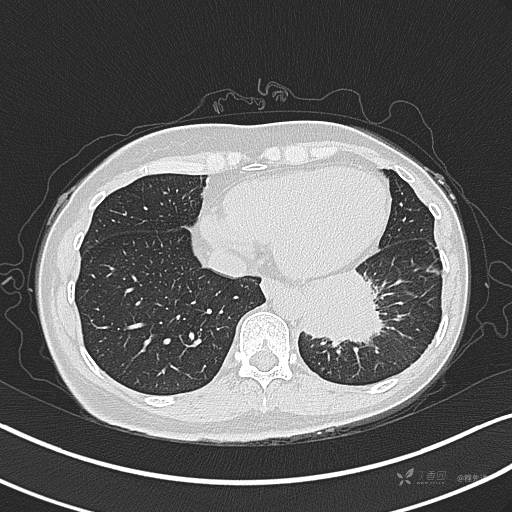

CT平扫

肺窗